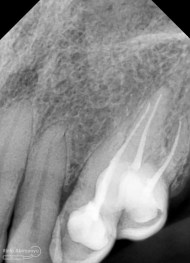

Pemeriksaan respon dingin pun menunjukkan hasil negatif, untuk menambah data dalam penegakan diagnosis maka dilakukan pengambilan ronsen pada gigi2 tersebut

Terlihat dari ronsen tersebut karies pada gigi 23 24 sudah mencapai pulpa… dari informasi pemeriksaan klinis dan ronsen maka didiagnosis gigi tersebut nekrosis.. Saya jelaskan kepada pasien mengenai kondisi gigi2 nya dan rencana perawatan yang akan saya lakukan…